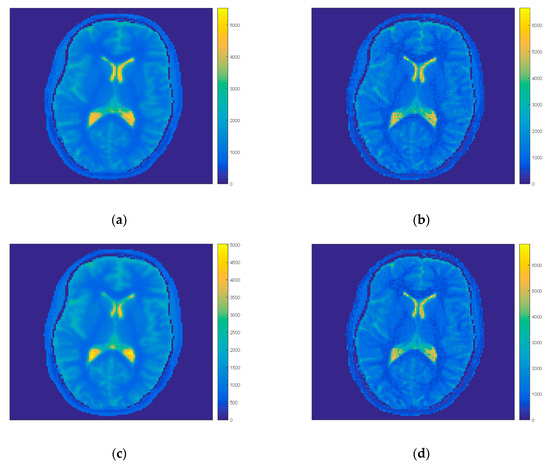

It was shown that an appropriate T1 evaluation was possible in reduced processing time using a strongly reduced number of projections, while the initial model was still calculated using all projections. If a reduction of projections was also possible in this first part of the data processing, the acquisition of the skipped projections could be omitted and data from parallel slices could be acquired in this time. A multi slice measurement in only 6 s would be then possible. For the IFM model the reconstruction scheme and evaluation of first model was possible for up to each second projection—for a higher number the initial model was noisy and the reconstruction generated a lower value of the mean/std. The power of the IFM model was connected to the number of points for which the interpolation could be performed. In the case of decreasing the number of projections, the number of interpolated points was also limited and the higher spatial resolution, which was the main advantage of the approach was not visible. In contrast to IFM, application of our MFM model gave more promising T1 maps. Table 4 (and Table A3 in Appendix A) and Figure 5 show results of MFM with each second and sixth projection proving that even after taking each sixth projection it was possible to reconstruct the final T1 map. For each second projection the change in ROI values (WM—1.4%, GM—0.2% and CSF—1.38%) and mean/std was still comparable to reference data, for each sixth projection differences increased (WM—1.4%, GM—2.14% and CSF—6.24%) but the results were still comparable showing that it was possible to use the FIR-MAP for multi-slice of five simultaneous slices for 999 time stamps.

Figure 5.

T1 maps of FIR-MAP for MFM taking each second (a), sixth (b) and seventh (c) projection in initial step and iteration process for volunteer V7. The spatial resolution and image quality decreases with the number of projections (from a to c).